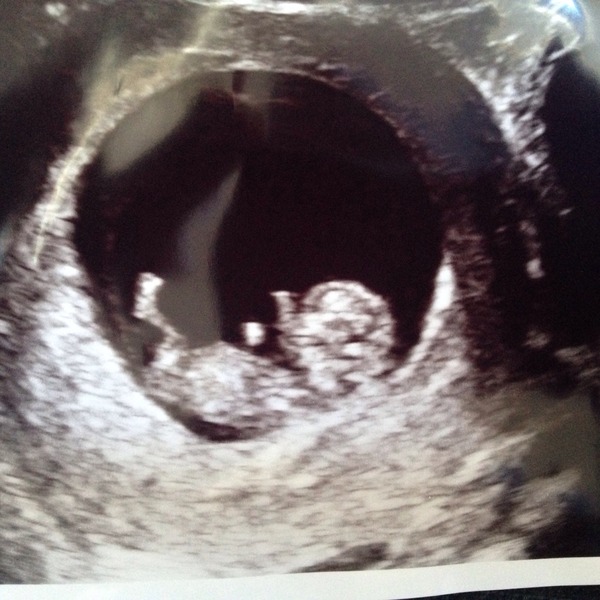

Peyia 30 London, OH is 35 and our DD is 3. I'm 8+6 and feel dreadful!!